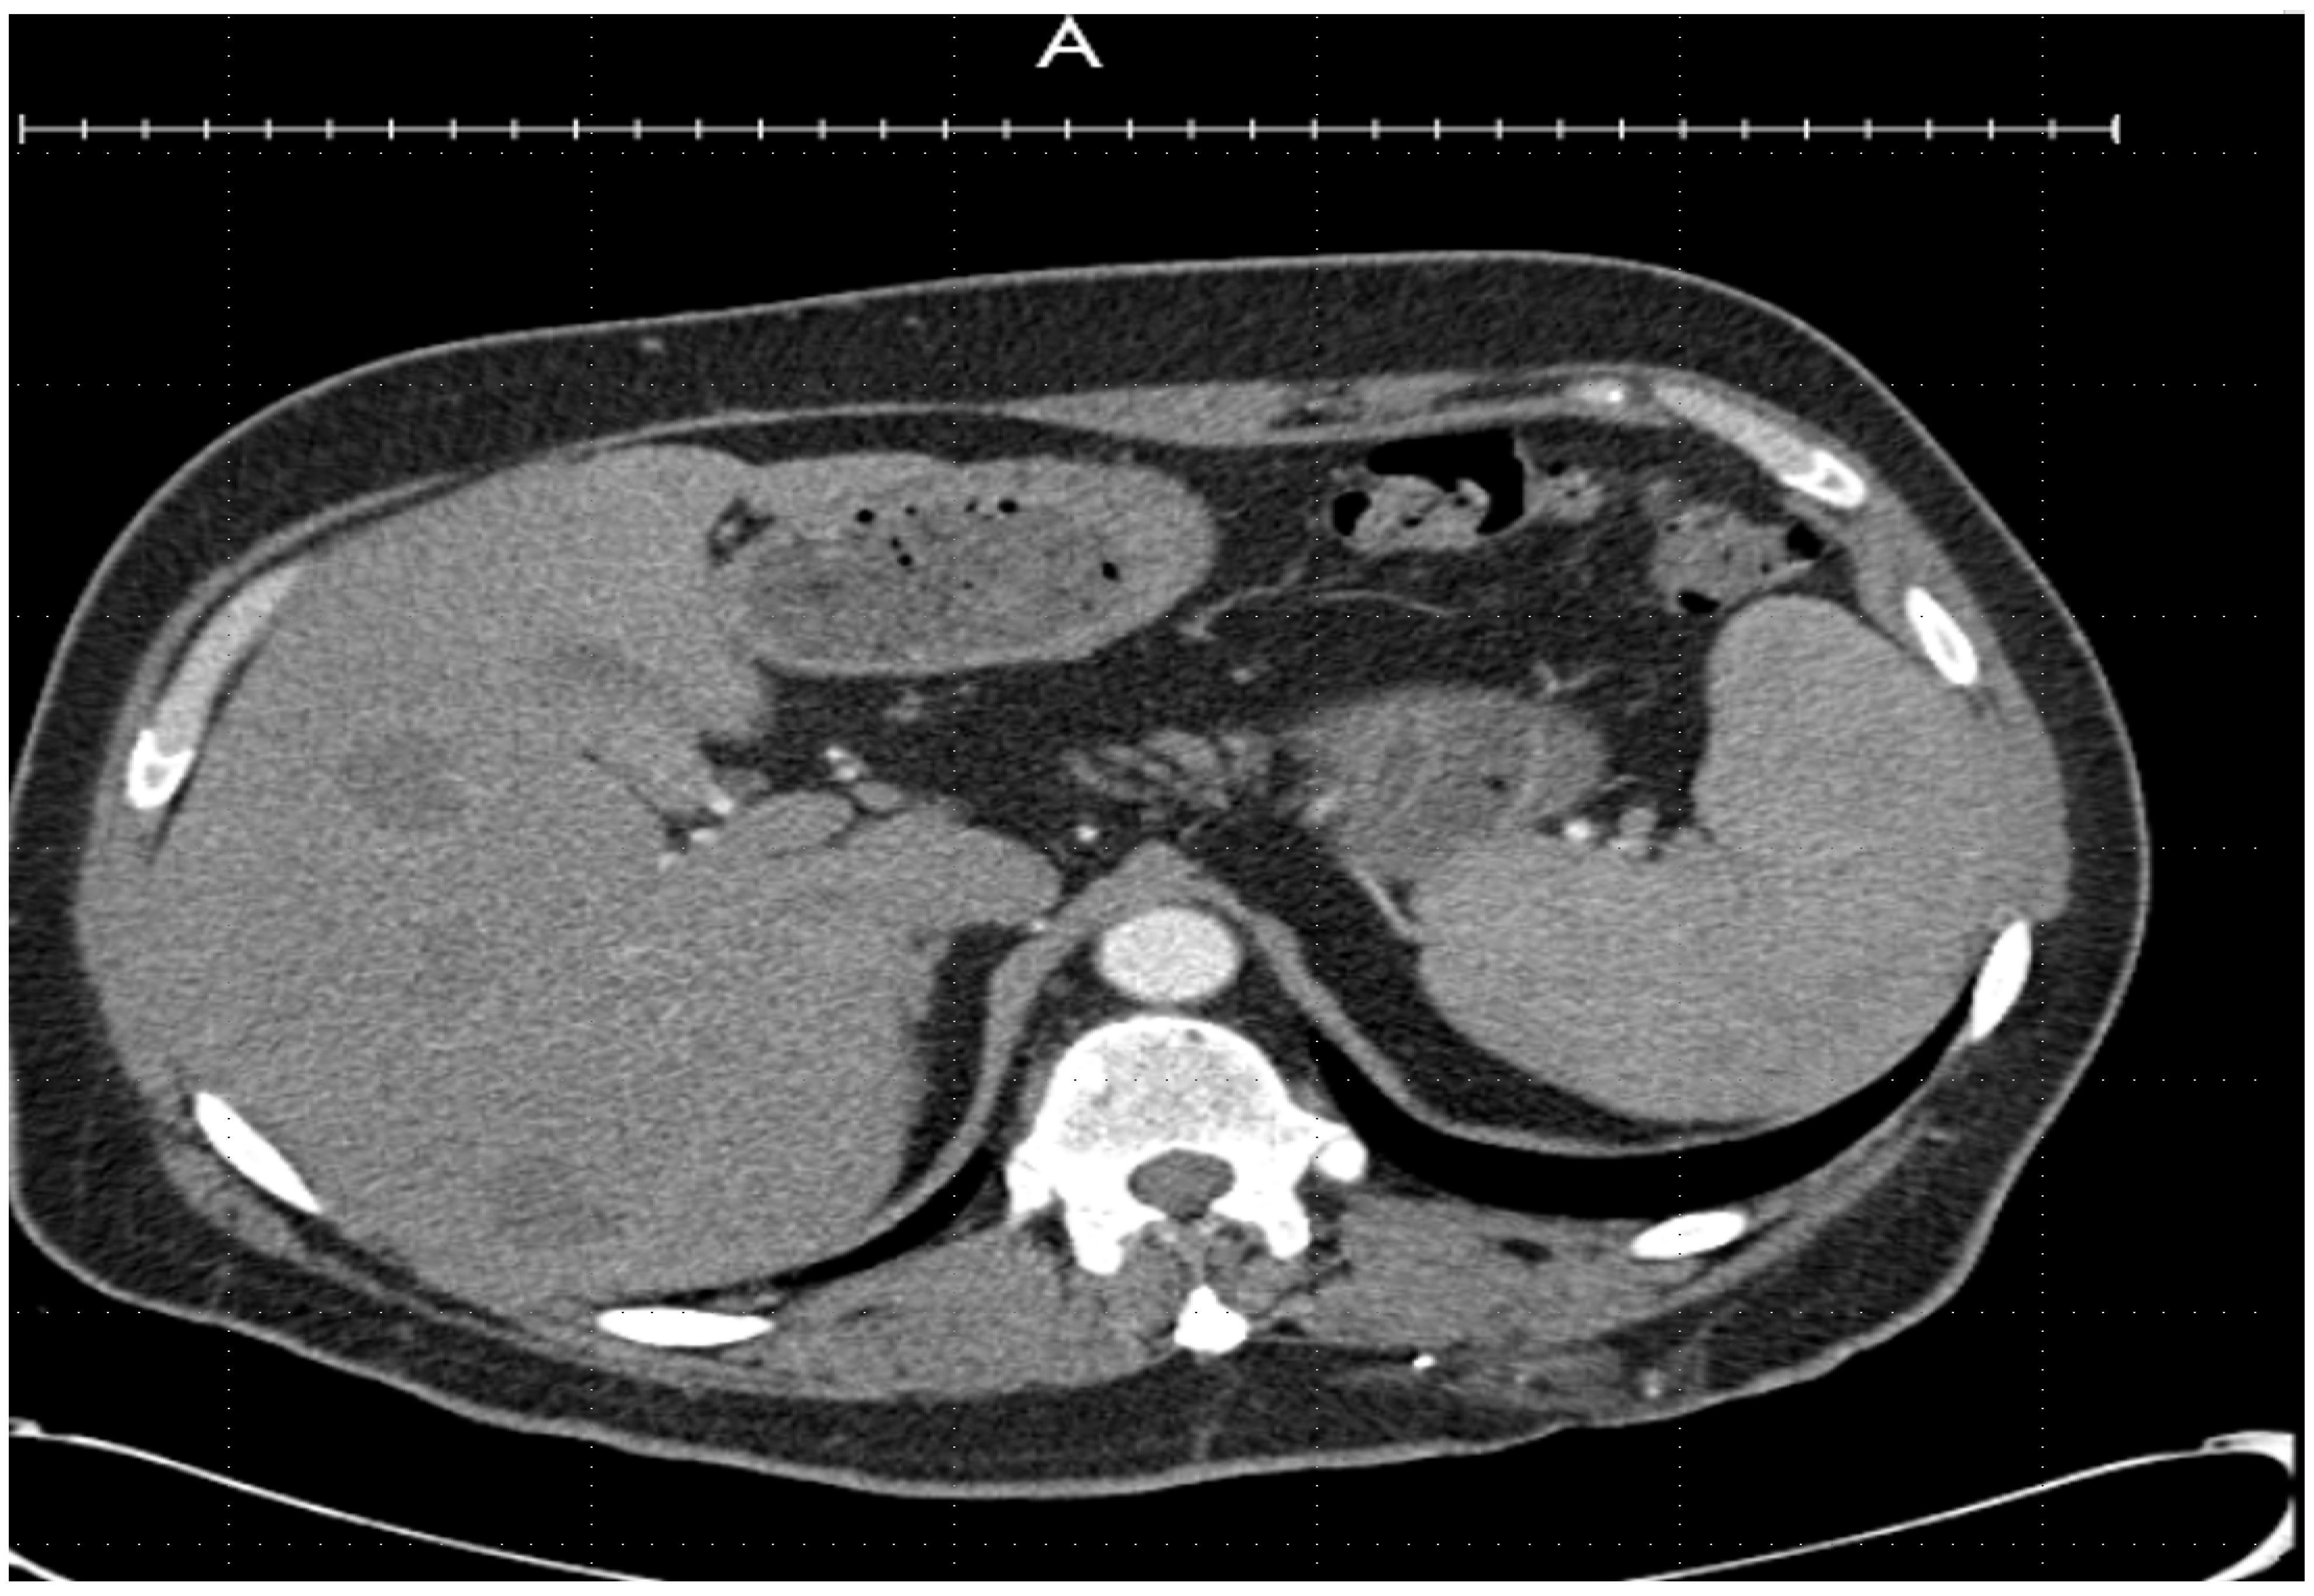

Imaging revealed multiple new hepatic lesions (Figure 2 and Figure 3), bilateral pulmonary nodules, and a new 2.9-cm left adrenal nodule, favoring a diagnosis of a metastatic tumor. The patient was admitted to the hospital for a higher level of care.

Figure 3.

Coronal Computed tomography imaging showing multiple new hepatic lesions.